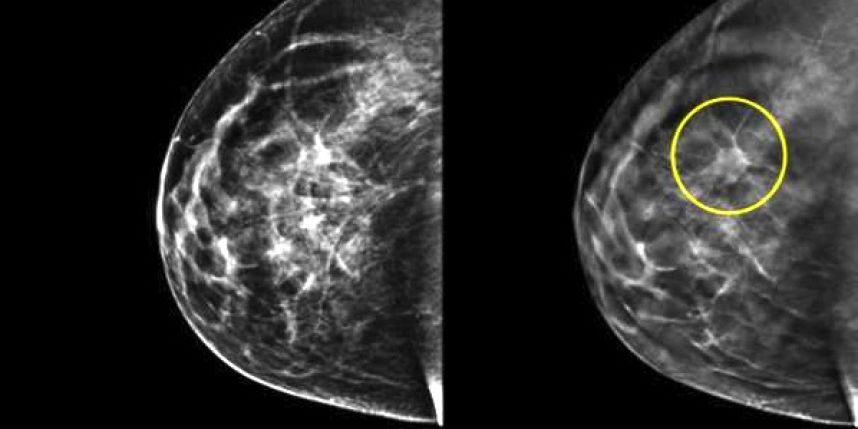

Question : Pour le cancer du Sein, dans quelle mesure les examens radiologiques permettent la comparaison de l’évolution de la lésion cancéreuse avant et après traitement ?

Dr BOUMEHDI Bounhir : Le cancer du sein représente la localisation cancéreuse la plus fréquente et la première cause de mortalité prématurée par cancer chez la femme. Bien que son incidence ne cesse d’augmenter, le taux de survie chez la femme porteuse d’un cancer du sein a été nettement amélioré durant les dernières décennies. Cette amélioration est liée aux campagnes de dépistage (voir l’opinion du 24 Mai 2016), à l’utilisation de traitement de plus en plus efficaces et au développement des techniques d’imagerie, permettant un diagnostic précoce. De plus le développement d système BI-RADS a largement contribué à l’amélioration de la qualité de la prise en charge. Son but est de permettre la standardisation des comptes rendus et de faciliter la comparaison entre examens successifs